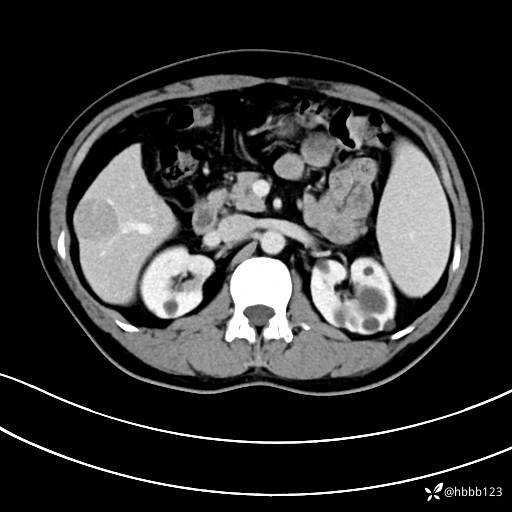

平扫: